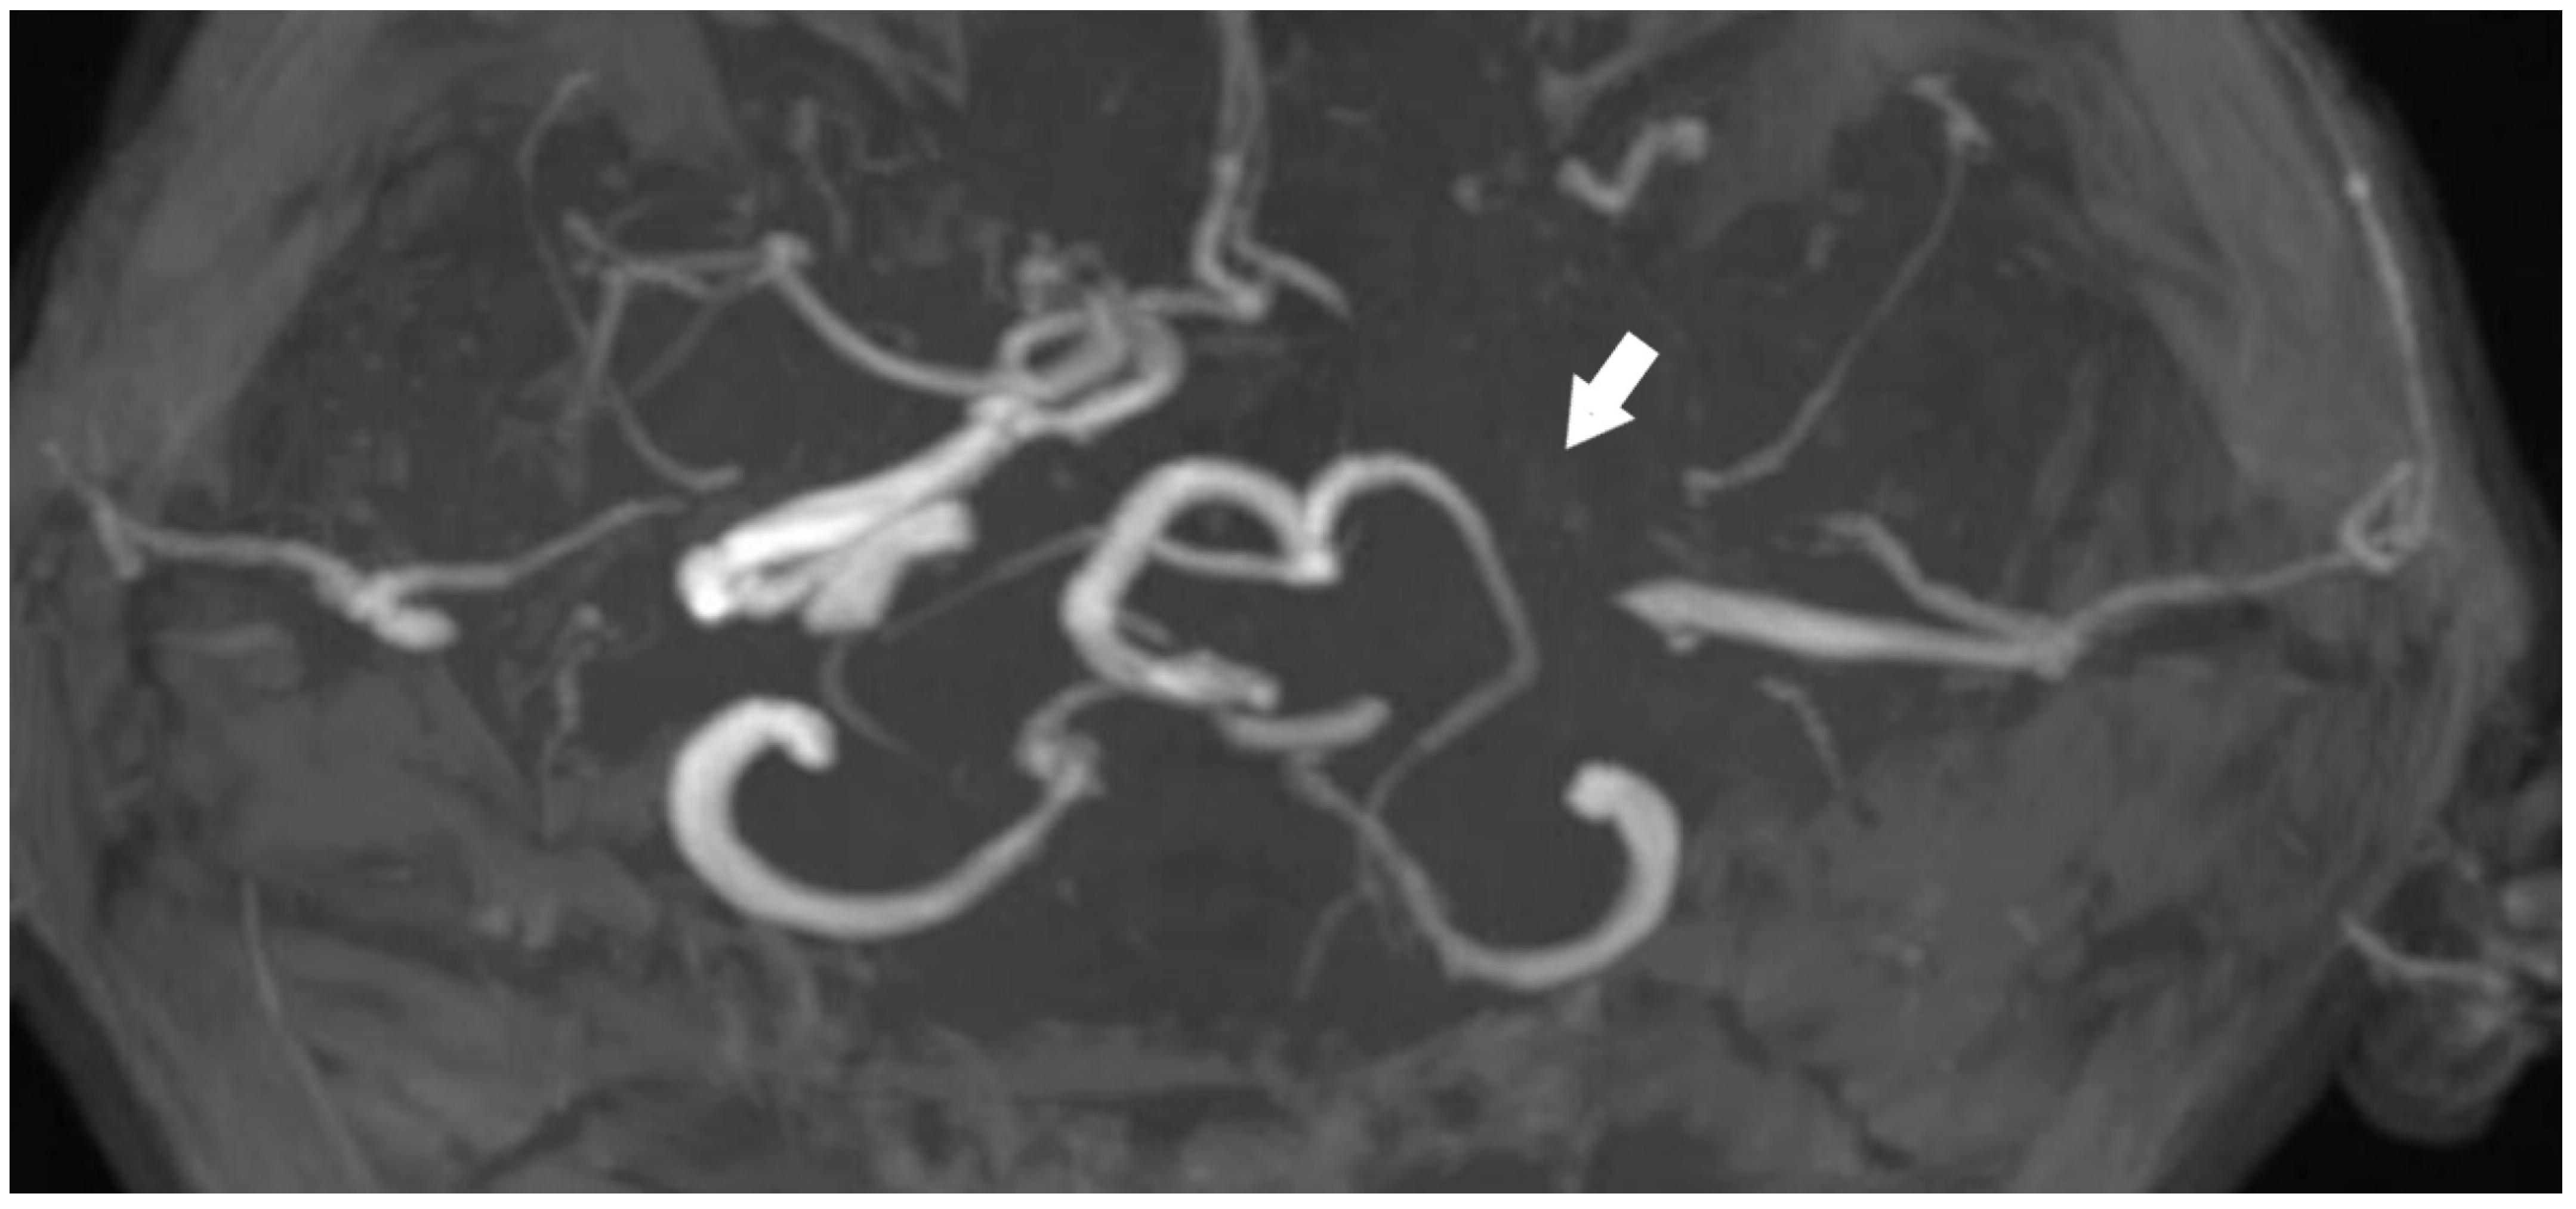

A review of the patient’s radiologic records revealed a cranial CT angiography performed nine years ago. Imaging showed no contrast in the left internal carotid artery. In addition, the left petrosal carotid canal was found to be intact (Figure 5 and Figure 6).

Figure 5.

CTA image obtained from the patient nine years ago [White arrow: indicates a filling defect beginning at the proximal segment of the ICA].

3. Results

CT imaging demonstrated a well-developed carotid canal, strongly favoring the diagnosis of chronic ICA occlusion rather than congenital agenesis. This underscores the importance of assessing the carotid canal in differentiating between these two entities. At the time of the patient’s initial presentation, MR angiography performed in our clinic suggested ICA agenesis, as there was no history of recurrent ischemic events. However, review of prior imaging revealed a CT angiography obtained nine years earlier, which confirmed the diagnosis of ICA occlusion. Given the evidence of a patent carotid canal, MR-VWI was deemed unnecessary. Although surgical or endovascular treatment was advised, the patient declined intervention and opted for continued clinical surveillance. During the current presentation, antiplatelet therapy and symptomatic medical management were initiated in the outpatient setting, resulting in clinical improvement at 3 months of follow-up (VAS score: 2, TFI grade: 1). The patient was again counseled regarding the risks associated with chronic ICA occlusion, including the elevated risk of ischemic stroke, and revascularization strategies, including hybrid procedures (combining STA–MCA bypass with endovascular techniques in a single session), were once more discussed.